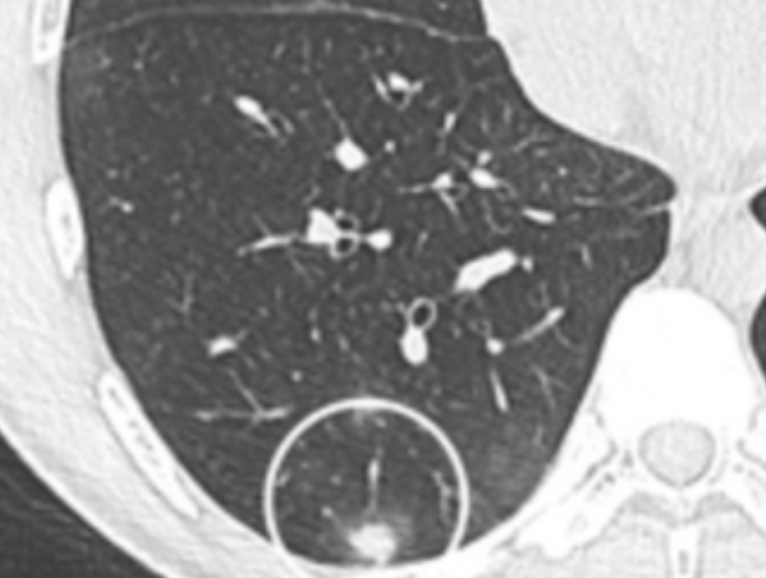

흉부CT는 이야기가 달라요. 얇게 자른 단면을 수백 장 촬영하기 때문에, 작은 병변도 놓치지 않습니다. 마치 산 전체를 한 장의 사진으로 보는 엑스레이와 달리, CT는 나무 한 그루 한 그루를 자세히 보는 느낌이에요. 예전에 병원에서 일했던 친구 말로는, 엑스레이에 아무 이상이 없던 환자가 CT에서 폐암 초기 진단을 받은 경우도 많았다고 합니다. 그만큼 CT는 정밀한 탐색 도구입니다.

흉부ct로 볼수있는 질환 폐질환뿐 아니라 심장과 혈관, 흉막, 림프절, 뼈 구조까지 한 번에 보여줍니다. 폐렴, 결핵, 폐기종, 기관지확장증, 간질성 폐질환 같은 호흡기 질환은 기본이고, 폐에 생긴 작은 결절이나 혹도 세밀하게 확인할 수 있습니다. 폐암이나 전이암처럼 초기에 증상이 거의 없는 병은 CT로 발견되는 경우가 많아요.

흉부CT는 병이 있는지 없는지를 넘어서, 병의 진행 정도와 주변 장기 침범 여부까지 보여줍니다. 예를 들어 폐암의 경우, 5mm 미만의 아주 작은 결절까지 찾아내고, 종양이 혈관이나 기관지에 닿았는지도 확인합니다. 초기에 잡아내면 완치율이 크게 높아지죠.

또한 폐렴이 감염인지, 결핵성인지, 종양에 의한 것인지도 구분할 수 있습니다. 엑스레이에서는 그냥 ‘흐린 그림자’로만 보이던 것도, CT에서는 염증의 경계와 내부 구조까지 뚜렷하게 드러납니다.